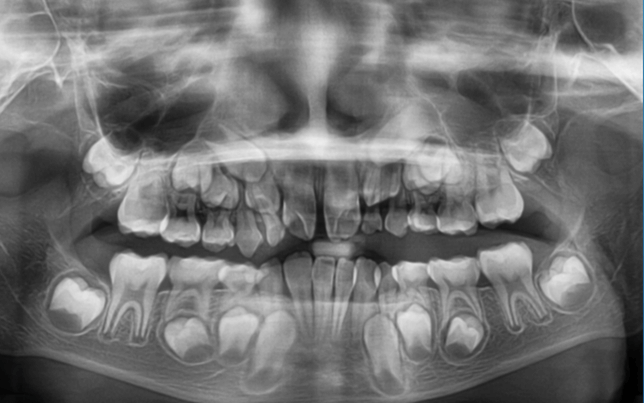

| 年齢・性別 | 8歳3ヶ月の男児 |

|---|---|

| 主訴 | 上顎前歯の位置異常に不安を抱え、歯並びと将来的な咬合状態を整える目的で来院された患者様です。 特に左側の前歯(中切歯および側切歯)の萌出が確認できないことがきっかけとなりました。 |

| 治療期間・回数 | 約5年10ヶ月 |

| 費用 | 460,000円(税別) |